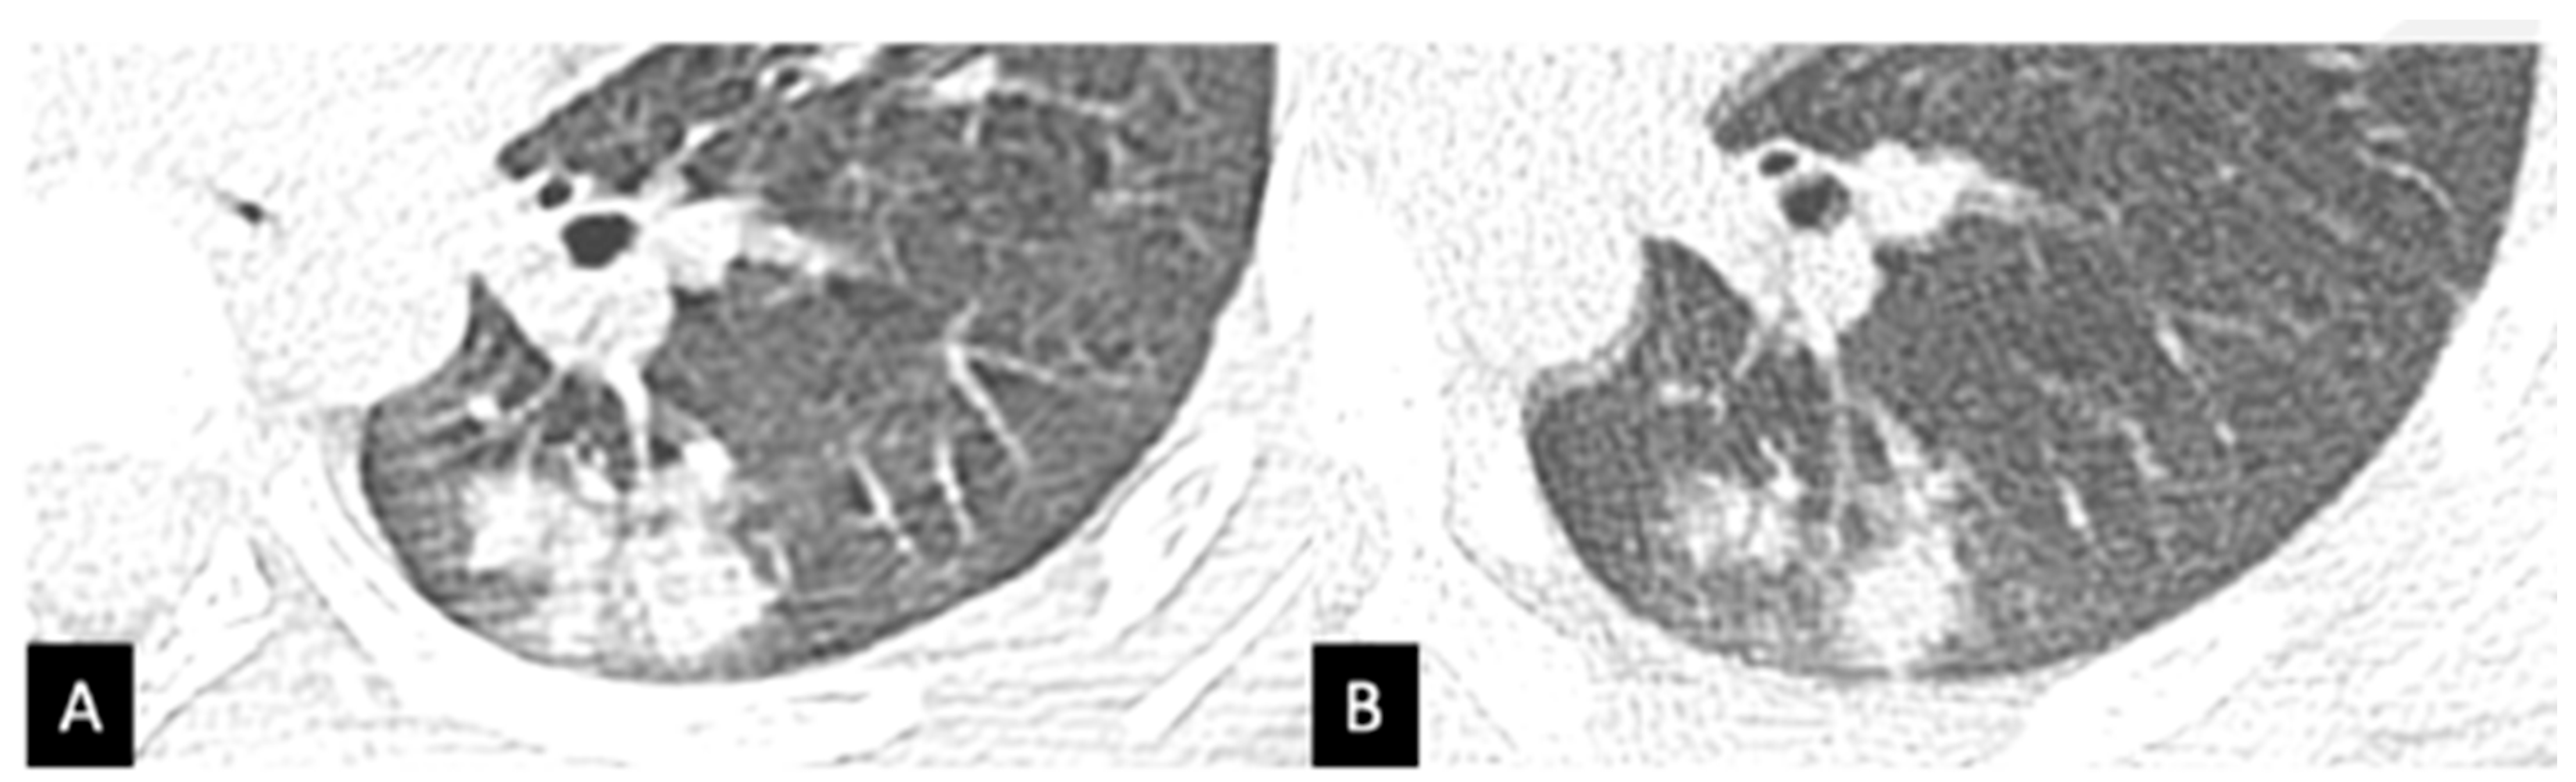

3.3. Case C

- Baratella, E.; Bussani, R.; Zanconati, F. Radiological-pathological signatures of patients with COVID-19-related pneumomediastinum: Is there a role for the Sonic hedgehog and Wnt5a pathways? ERJ Open Res. 2021, 7, 00346. [Google Scholar] [CrossRef] [PubMed]

- Baratella, E.; Ruaro, B.; Marrocchio, C.; Starvaggi, N.; Salton, F.; Giudici, F.; Quaia, E.; Confalonieri, M.; Cova, M.A. Interstitial Lung Disease at High Resolution CT after SARS-CoV-2-Related Acute Respiratory Distress Syndrome According to Pulmonary Segmental Anatomy. J. Clin. Med. 2021, 10, 3985. [Google Scholar] [CrossRef] [PubMed]